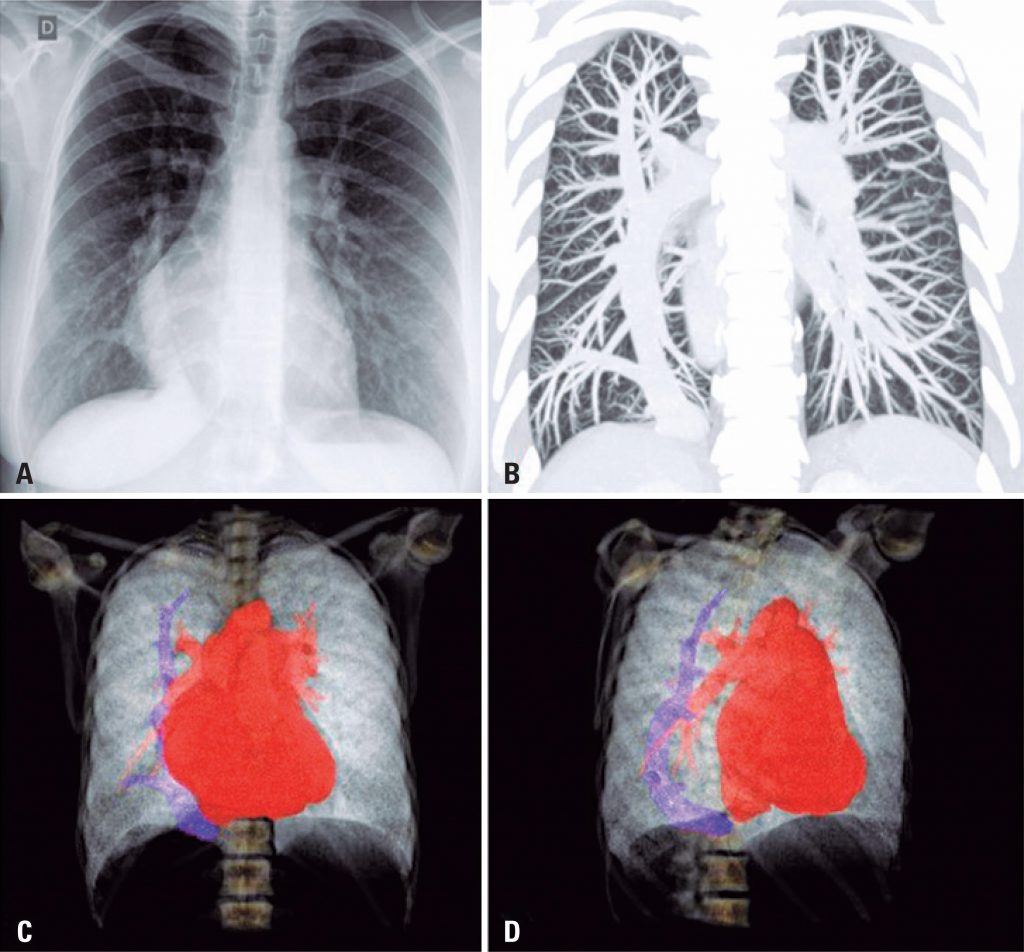

A 34-year-old patient with a history of asthma, taking inhaled corticosteroids and bronchodilators, presented with worsening dyspnea (functional class III) and reports of syncope. On physical examination, pulmonary auscultation was normal with pulse oximetry of 96% in room air. On cardiac auscultation, the rhythm was regular with fixed splitting S2 and systolic murmur 2+/6+ on left sternal border. On abdominal examination, the liver was palpable 2cm below the right costal border. There were no other signs of heart failure. Chest radiography was performed during the investigation, which showed a calibrous tubular structure slightly arched towards the right atrium and part of the cardiac area occupying the right hemithorax ( ). Chest CT scan revealed a large caliber anomalous vein in the right lung, draining into the cavoatrial junction ( ). Three-dimensional computed tomography scan using intravenous contrast showed a thick anomalous vein arched along the craniocaudal axis of the right lung, draining into the cavoatrial junction, compatible with scimitar ( and ).